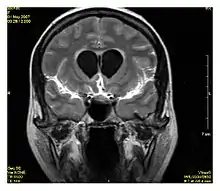

Neuroimaging

MRI diffusion tensor imaging of white matter tracts

MRI is the investigative tool of choice for neurological cancers over CT, as it offers better visualization of the posterior cranial fossa, containing the brainstem and the cerebellum. The contrast provided between grey and white matter makes MRI the best choice for many conditions of the central nervous system, including demyelinating diseases, dementia, cerebrovascular disease, infectious diseases, Alzheimer's disease and epilepsy.[30][31][32] Since many images are taken milliseconds apart, it shows how the brain responds to different stimuli, enabling researchers to study both the functional and structural brain abnormalities in psychological disorders.[33] MRI also is used in guided stereotactic surgery and radiosurgery for treatment of intracranial tumors, arteriovenous malformations, and other surgically treatable conditions using a device known as the N-localizer.[34][35][36] New tools that implement artificial intelligence in healthcare have demonstrated higher image quality and morphometric analysis in neuroimaging with the application of a denoising system.[37]